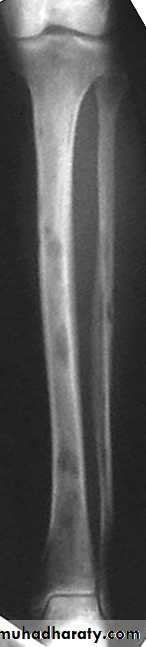

AVN occurs primarily in medullary space of long bones, hands, growing

epiphyses

* Bone sclerosis from infarctions

* Dactylitis (hand-foot syndrome): bone infarcts of hands and feet

Most commonly at diaphysis of long bones

Plain radiography. Anterior-posterior view of bilateral knees. Note the irregular areas of lacy and serpentine calcific deposits in bilateral distal femurs and proximal tibias typical for bone infarcts.